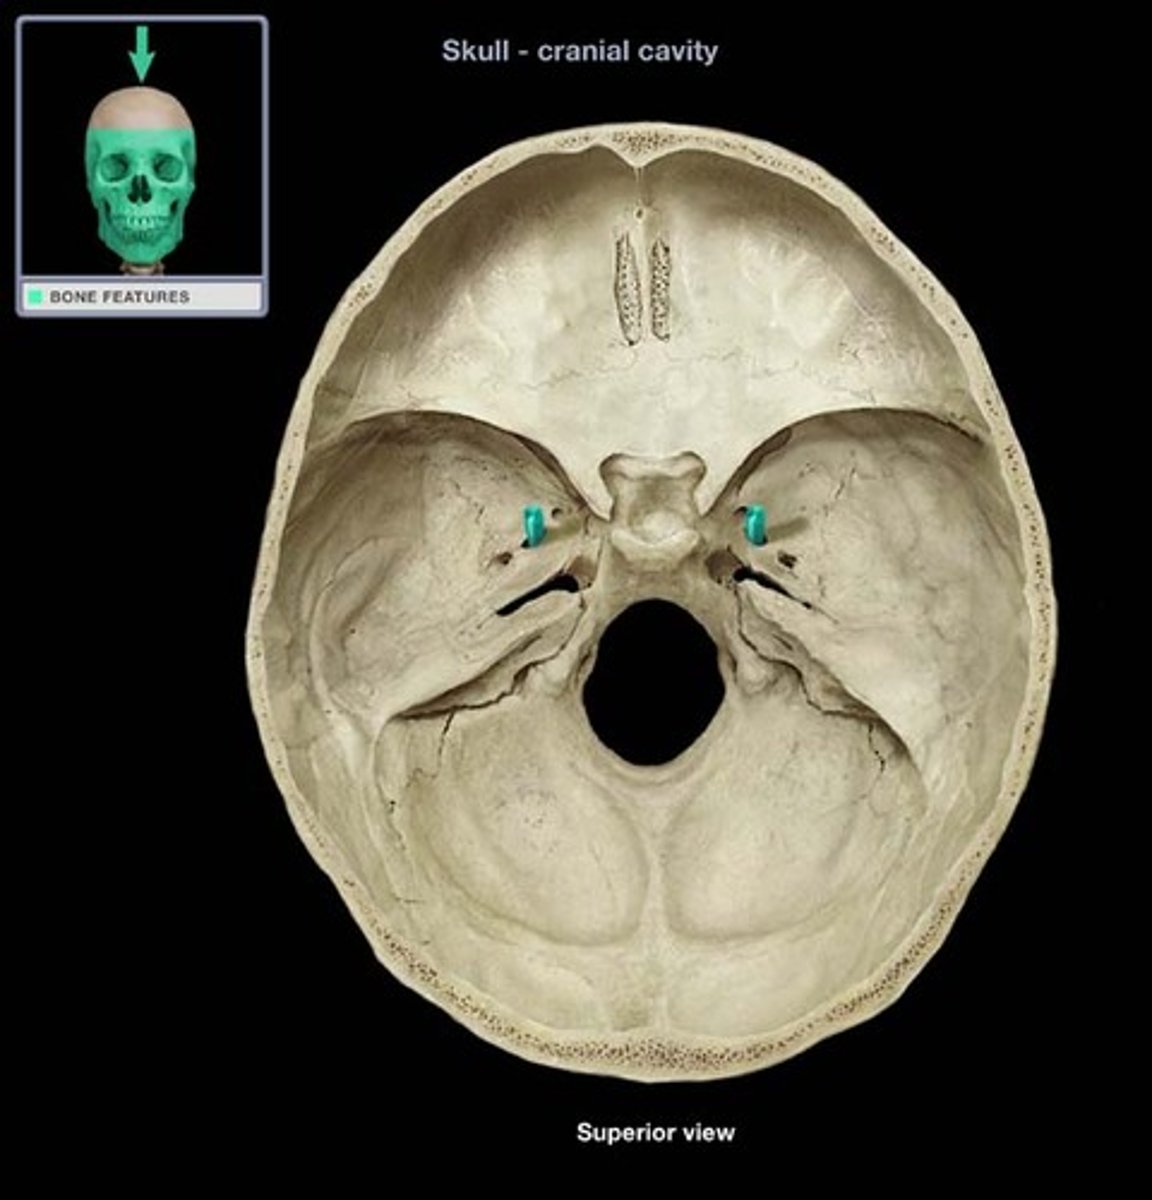

carotid canal

jugular foramen

Name this structure.

internal acoustic meatus